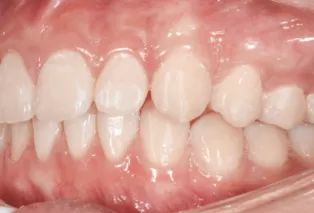

Intraoral photos after treatment